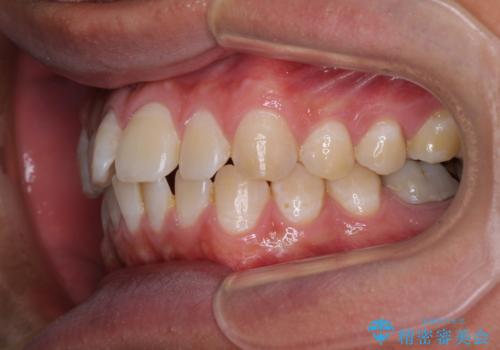

- 前歯のデコボコを気にして来院された患者様です。

ワイヤー装置でもマウスピースでも対応可能でしたが、自己管理の煩わしさを気にされ、ワイヤー装置にて矯正治療を行うこととしました。